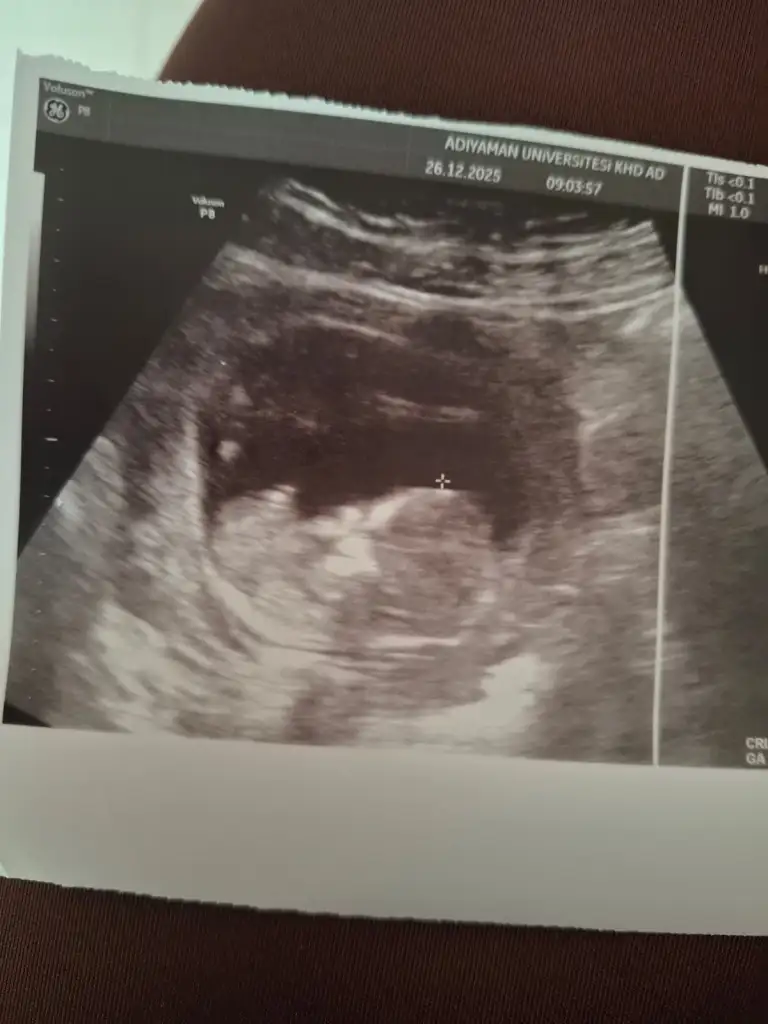

Nub teorisi cinsiyet

Sizce cinsiyeti nedir ? Tahmin alabilir miyim 🤭

Benimkini de yorumlar mısınız 11 haftalık 😊